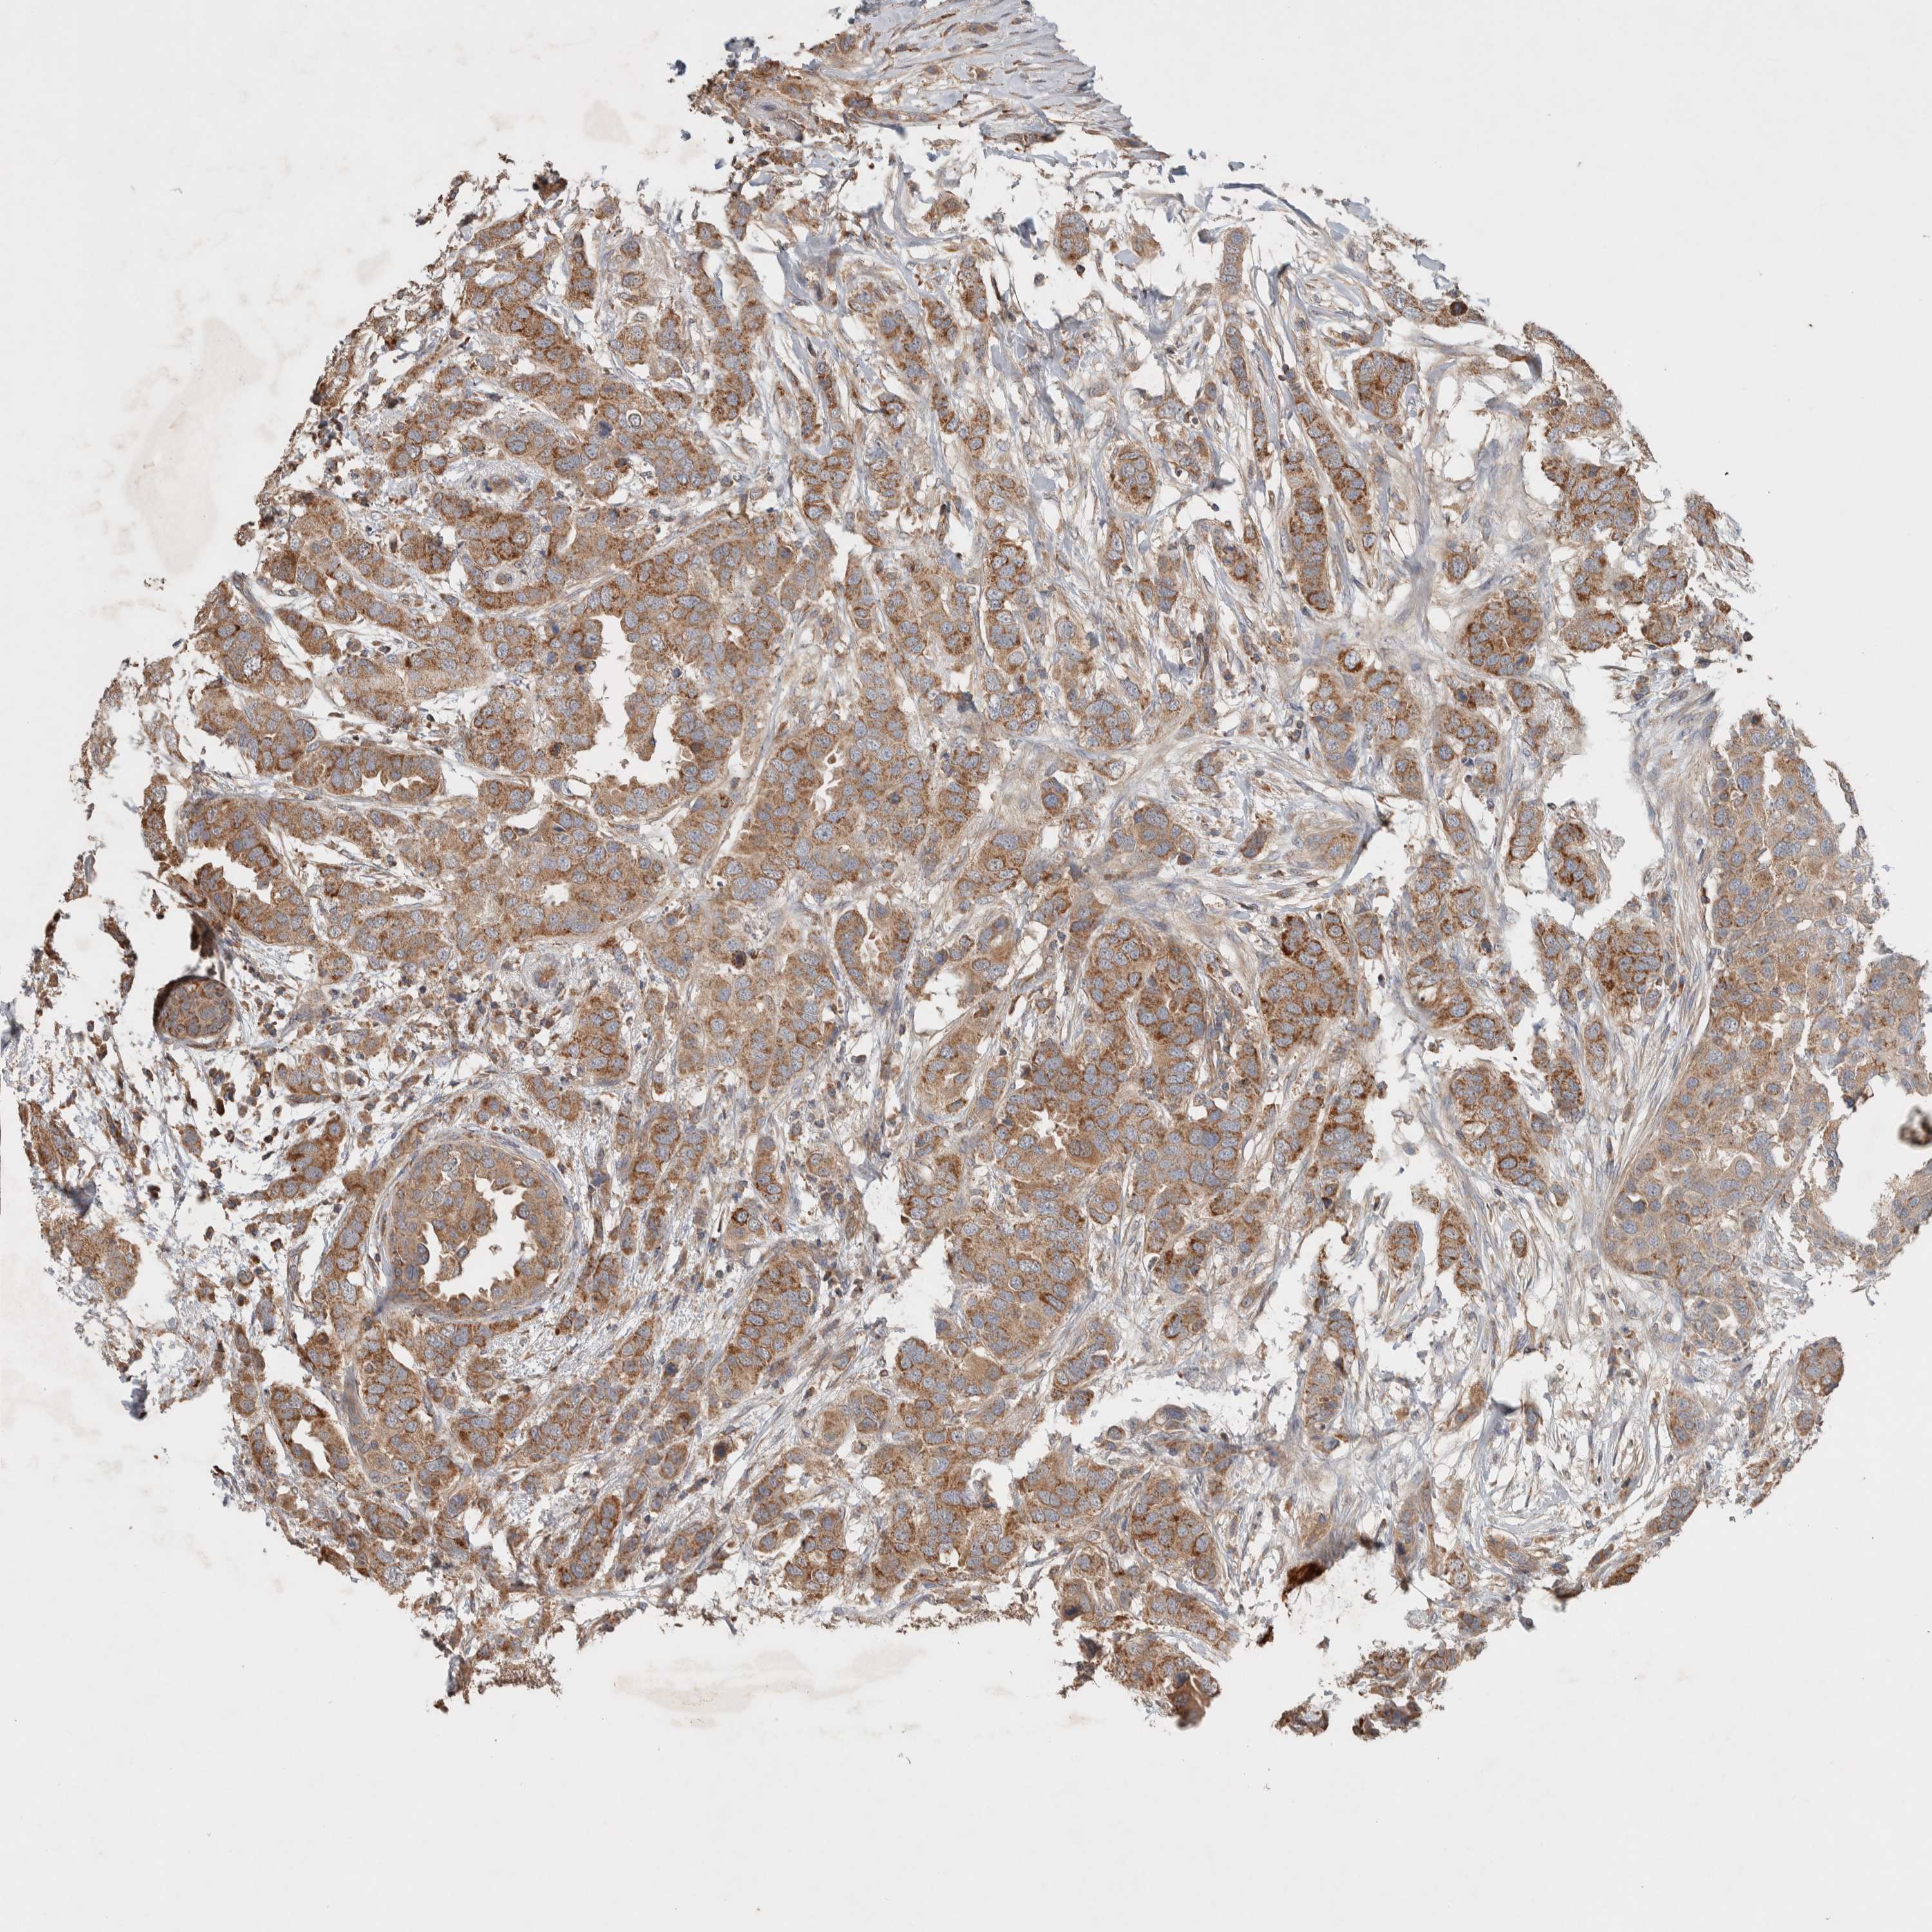

CANCER BREAST CANCER Show tissue menu

BRCA TCGA BRCA VALIDATION PROTEIN EXPRESSION